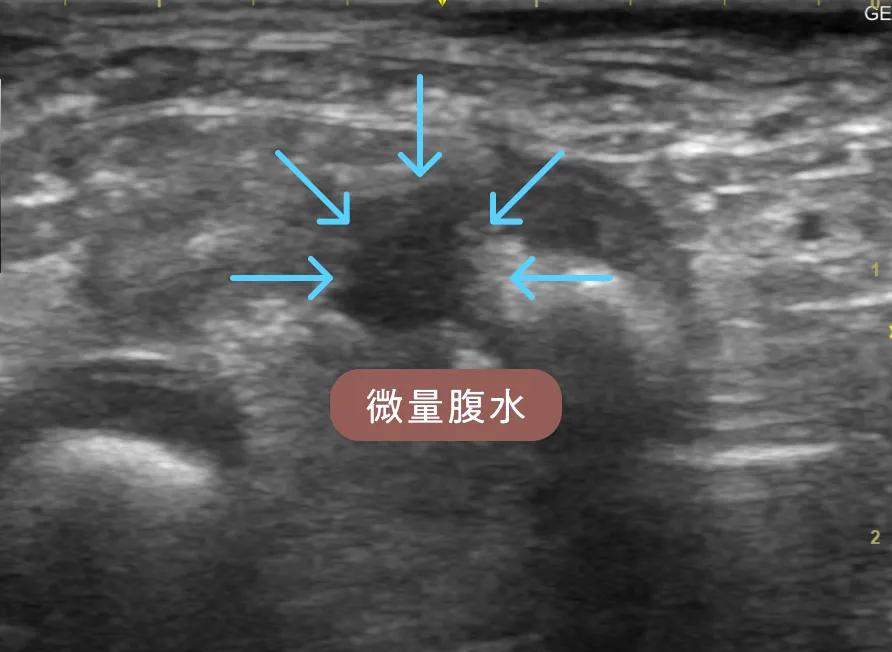

身体検査では軽度の削痩を認めました。血液検査では低アルブミン血症(2.1 g/dl)を認めました。エコー検査では小腸の広範囲でリンパ管拡張を示す白い縦縞のストリエーションサイン(正常な腸には見られない、エコーで映る縞模様 _ 赤矢印)と微量腹水(青矢印)が見られました。